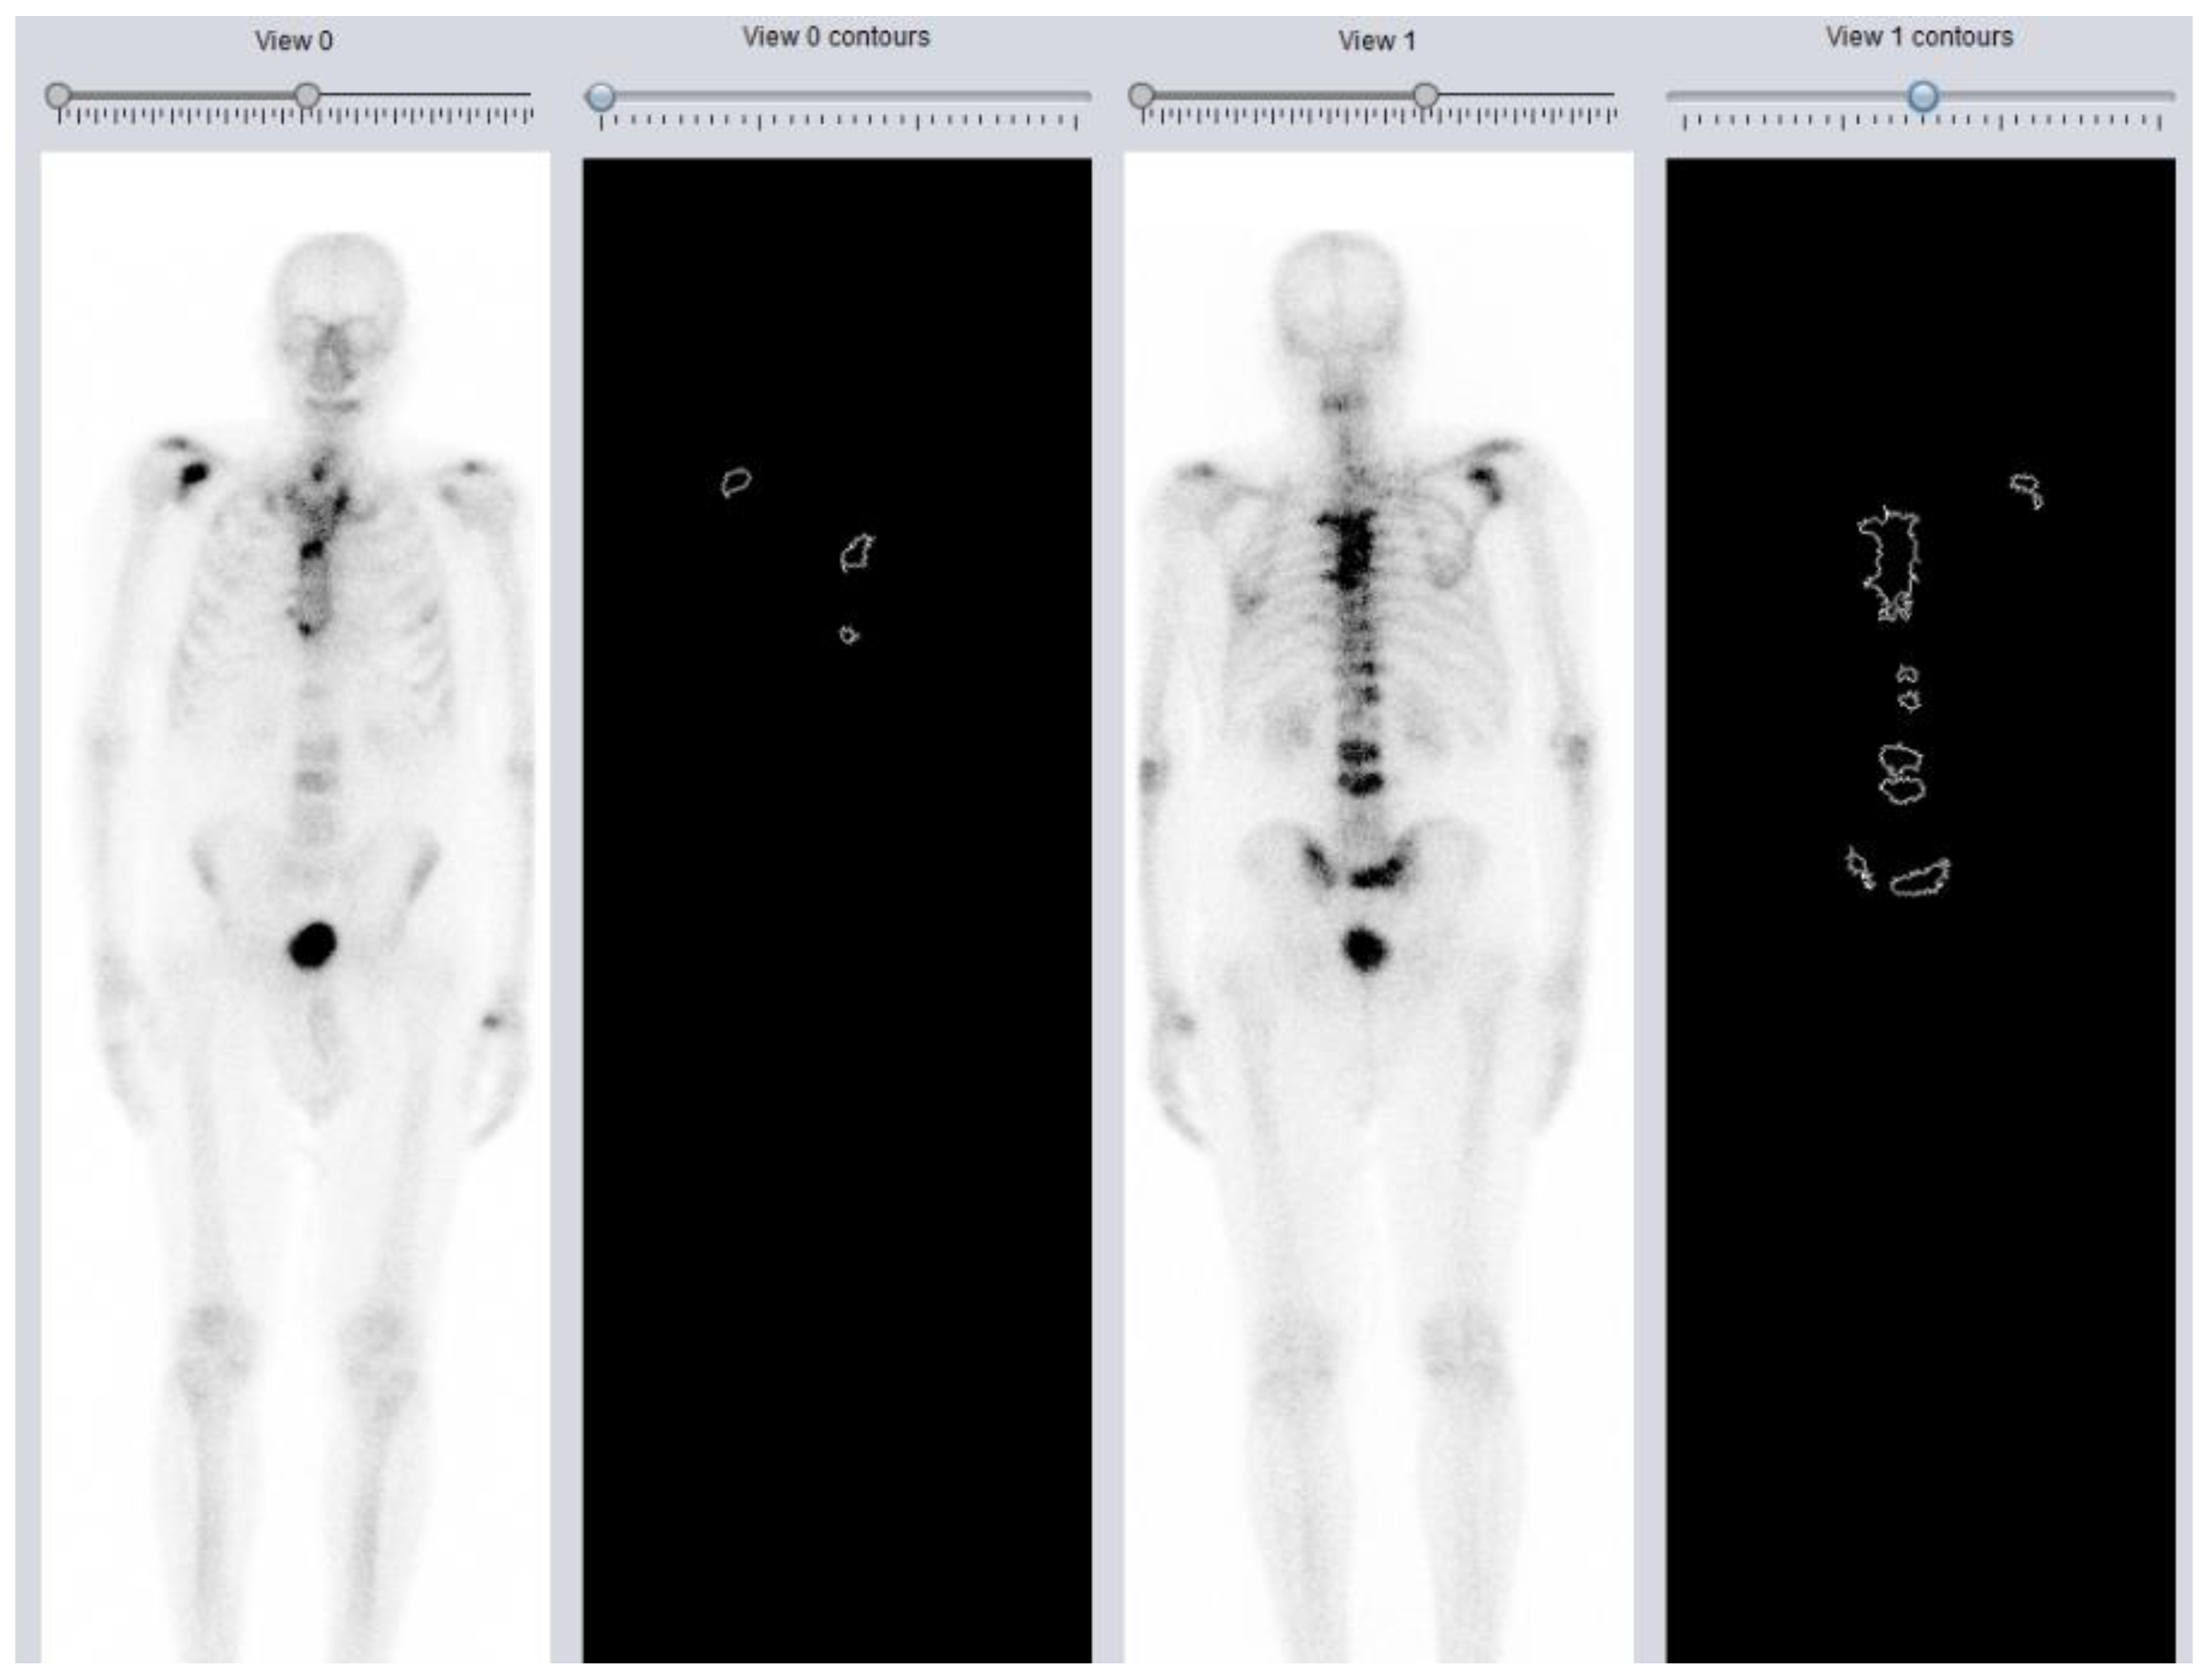

1.3. DASciS Software for BSI Calculation

2.1. DASciS Software